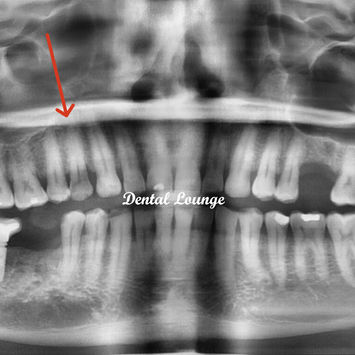

Cracked Tooth Removal of Tooth #14 with Dense Bone and Long Roots

CBCT results: Tooth #14 has two roots, long and divergent, with dense bone.

Surgery noted as very difficult due to dense bone and the need to conserve bone for future implant restoration.